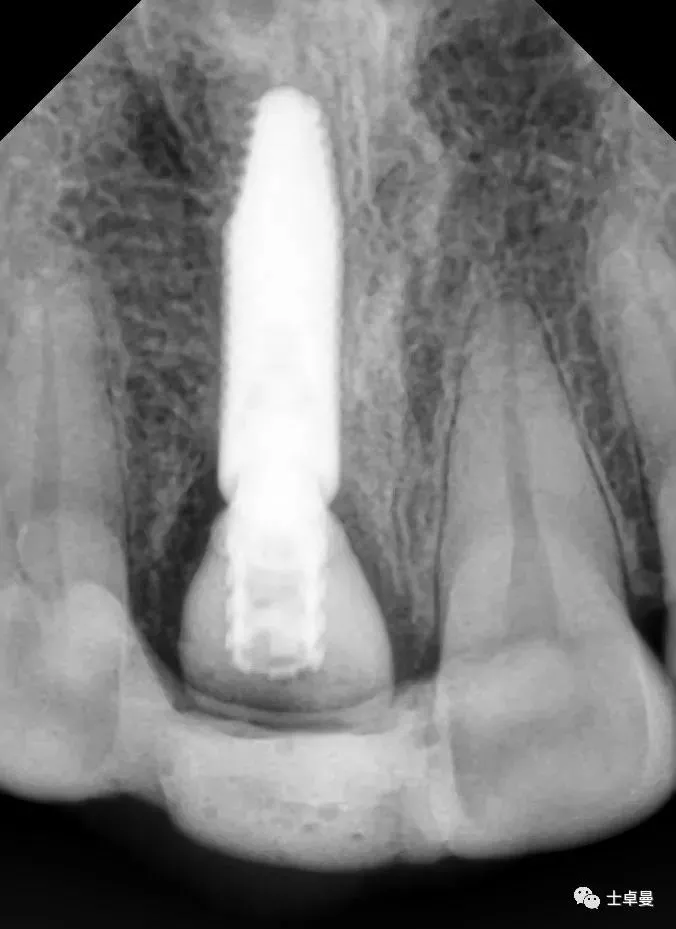

术后即刻CT示,种植体植入位置理想

术后4个月复查,种植体周未见明显暗影

X线片示,临时修复体已就位

X线示,永久修复体已就位